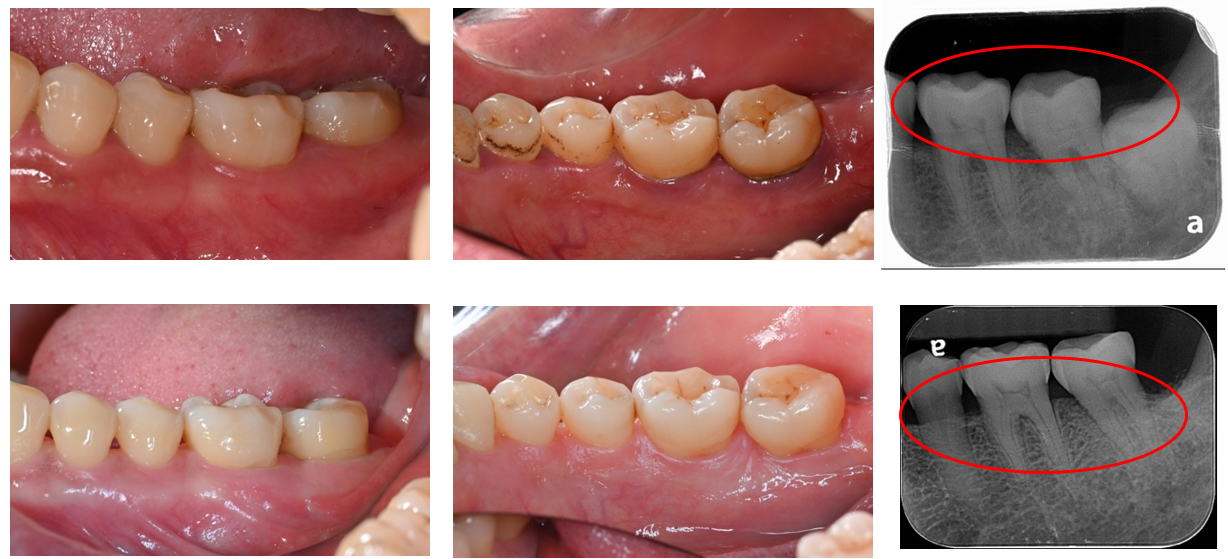

附圖為筆者案例,患者經過牙周治療後,口腔清潔能力改善,重建缺損的牙周組織,減少牙齒動搖度,獲得期待的生活品質。